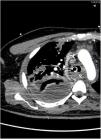

Un varón de 38 años sin antecedentes médicos relevantes, fue hospitalizado en la unidad de cuidados intensivos con fiebre y síntomas respiratorios inespecíficos, que progresaron rápidamente a insuficiencia respiratoria grave, shock séptico y fracaso multiorgánico. Requirió soporte vasopresor, ventilación invasiva y tratamiento antibiótico con penicilina, clindamicina y linezolid al aislar Streptococcus pyogenes en muestras respiratorias y hemocultivos. A pesar del tratamiento, persistieron la fiebre, al igual que una consolidación en la radiografía de tórax (fig. 1, flecha). La tomografía computarizada reveló necrosis (fig. 2, estrella) y absceso (fig. 2, flecha) pulmonar en el lóbulo superior derecho. Este caso destaca una presentación grave de infección invasiva por S. pyogenes, resaltando la necesidad de considerar esta etiología en el diagnóstico diferencial, incluso en pacientes sin factores de riesgo conocidos.